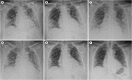

We report a rapidly deteriorating coronavirus disease 2019 (COVID-19) patient, a-58-year-old woman, with severe acute respiratory distress syndrome and shock with hyperpyrexia up to 41.8°C, probably due to the cytokine storm syndrome. Considering extracorporeal membrane oxygenation (ECMO) as the last resort, we applied therapeutic temperature modulation for management of hyperpyrexia. The patient demonstrated rapid improvement in oxygenation and shock after achieving normothermia, and fully recovered from COVID-19 three weeks later. Therapeutic temperature modulation may have successfully offloaded the failing cardiorespiratory system from metabolic cost and hyperinflammation induced by hyperpyrexia. The therapeutic temperature modulation can safely be applied in a specific group of patients with cytokine storm syndrome and hyperpyrexia, which may reduce the number of patients requiring ECMO in the global medical resource shortage.